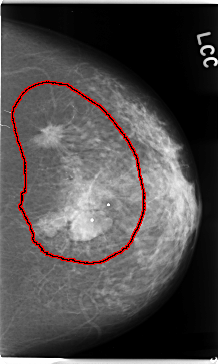

FILE: C_0112_1.LEFT_CC.OVERLAY

TOTAL_ABNORMALITIES 1

ABNORMALITY 1

LESION_TYPE MASS SHAPE IRREGULAR MARGINS SPICULATED

ASSESSMENT 5

SUBTLETY 5

PATHOLOGY MALIGNANT

TOTAL_OUTLINES 1

BOUNDARY